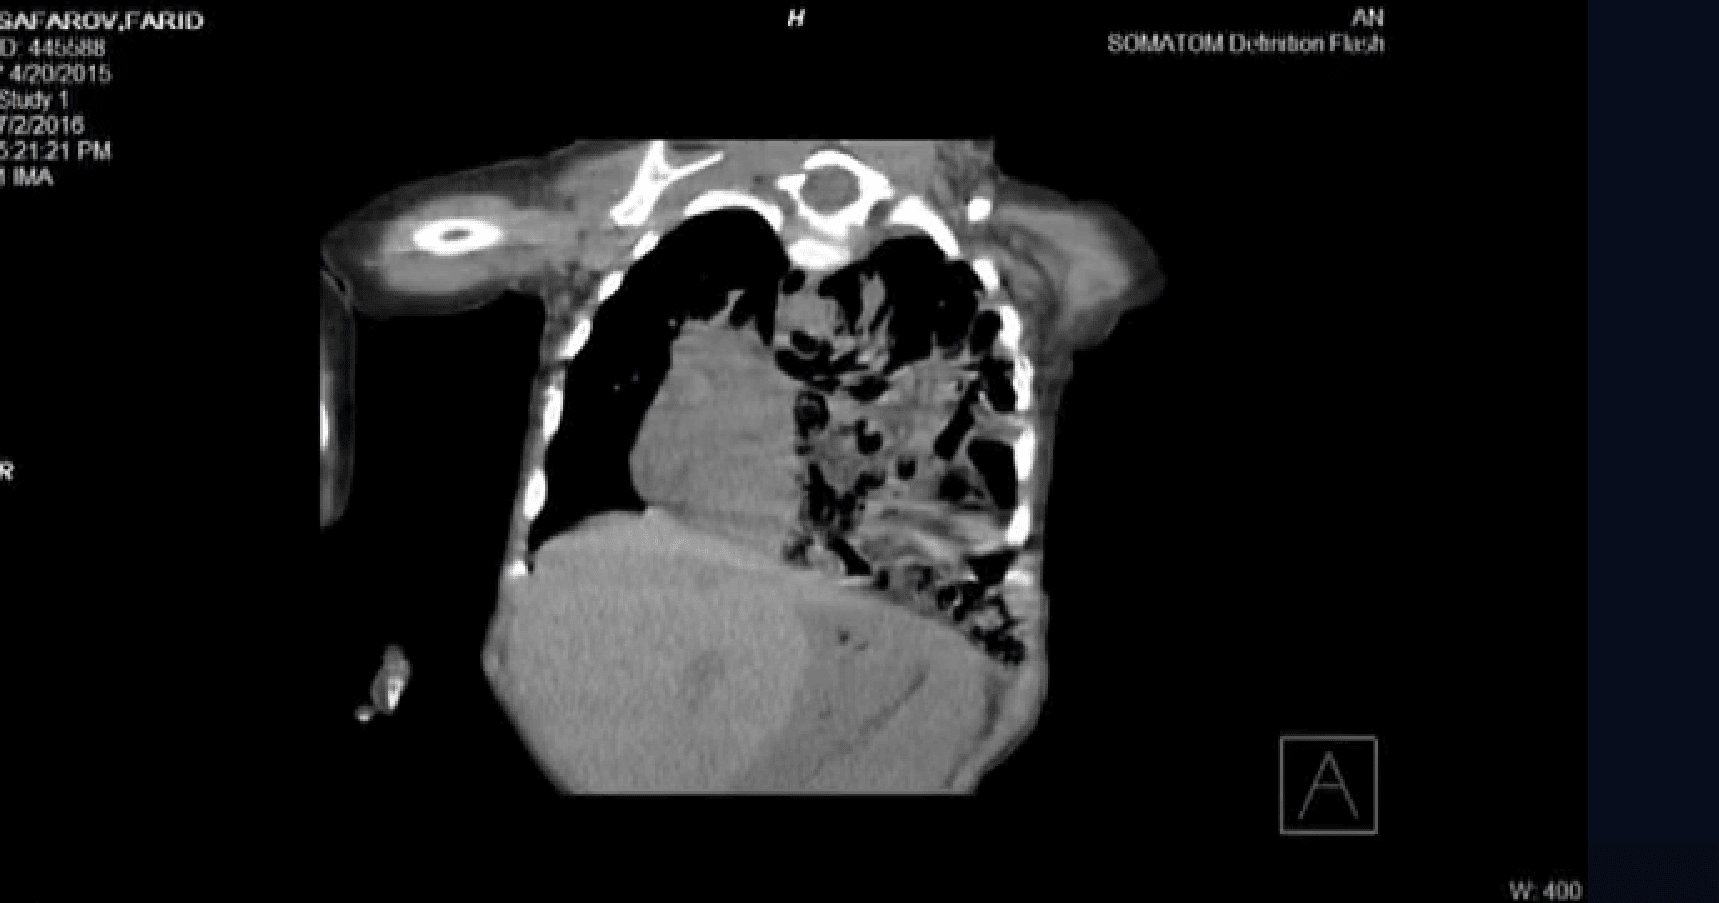

- Diafraqmal yırtıq təmiri (transtoraksik)